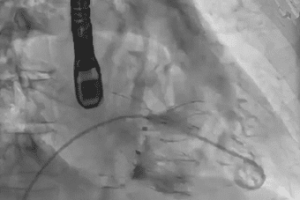

12 décembre 2023 « Des perspectives importantes dans le domaine de la cardiologie interventionnelle structurelle »